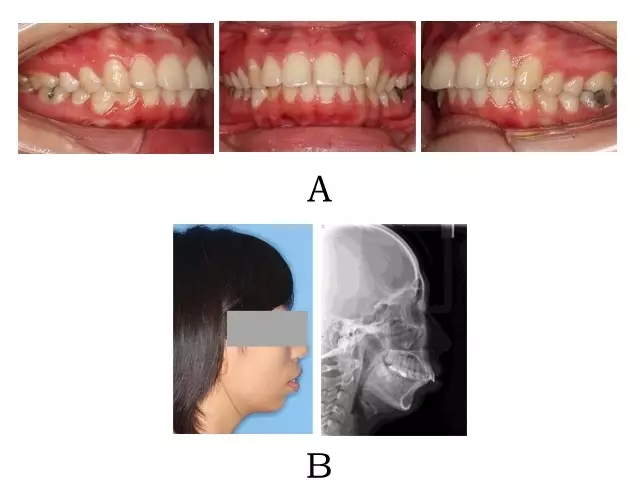

面下部前突,上頜前突、下頜后縮,唇態(tài)往往呈閉合不全。上頜前部齒槽前突,根形不明顯,整個牙槽肥大,肉眼觀察骨粘膜張力大。上前牙呈直立(骨源 I 型)或內(nèi)傾(骨源 II 型),上下前牙覆合覆蓋在正常范圍。頭顱側位片往往顯示下頜骨體部呈“三角形”,頦部向下旋轉(zhuǎn),常表現(xiàn)為高角(下頜后縮)(圖 2-1)。

圖 2-1:骨源性突面畸形臨床表現(xiàn)及頭顱側位影像特征。

(A)齒槽與牙列特點 (B)側貌與影像對比

Figure 2-1. Clinical manifestation and cephalometric image for alveolar prognathism. (A) Alveolar and dentition specifics. (B) Facial profile and radiographic image.